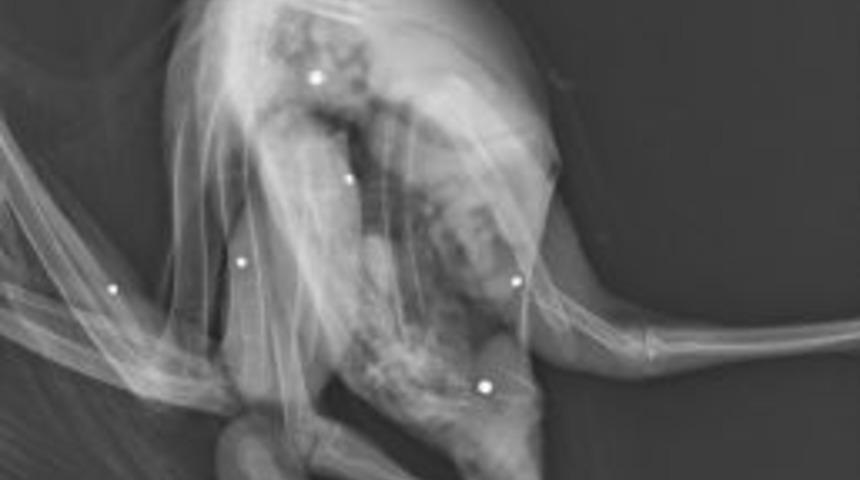

Yalova’da vatandaşlar tarafından yaralı halde bulunan kızıl şahin, Doğa Koruma ve Milli Parklar Müdürlüğü ekiplerine teslim edildi.Edinilen bilgiye göre, yaralı olarak bulunan kızıl şahin, vatandaşlar tarafından Doğa Koruma ve Milli Parklar 2. Bölge Yalova Şube Müdürlüğüne getirildi. Yapılan muayenede şahinin kırık ve yaralarının olduğu tespit edildi. Çekilen röntgende kızıl şahinin ateşli silah ile yaralandığı, vücudunda çok sayıda saçma bulunduğu tespit edildi. Şahin ameliyat edilerek müşahede altına alındı. Şahini vuran avcı ya da avcıların tespit edilmesine çalışılıyor.